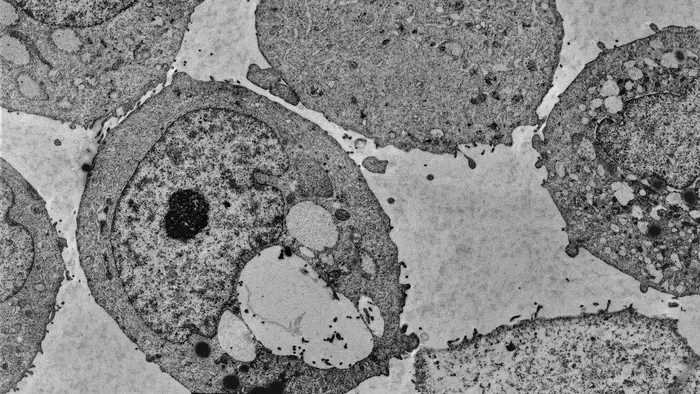

When mice with prostate cancer are given menadione, it messes with the cancer’s survival processes. Trotman’s team has discovered that menadione kills prostate cancer cells by depleting a lipid called PI(3)P, which works like an ID tag. Without it, the cells stop recycling incoming materials and eventually explode.

“It’s like a transport hub, like JFK. If everything that goes in is immediately de-identified, nobody knows where the airplanes should go next. New stuff keeps coming in, and the hub starts to swell. This ultimately leads to the cell bursting," explains Trotman.